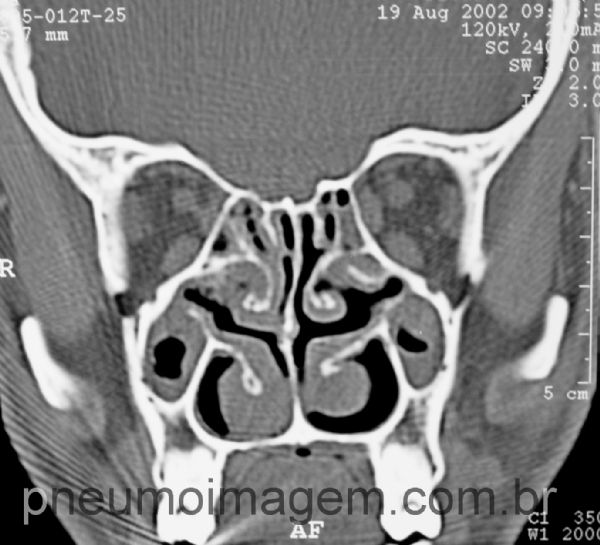

Síndrome de Kartagener. Inversão visceral (dextrocardia), bronquiectasias e sinusite.

Pan-sinusite.

chronic sinusitis.